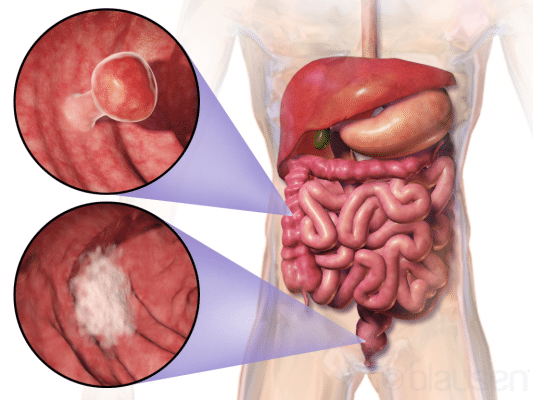

Καρκίνος του παχέος εντέρου

Οι ερευνητές διαπίστωσαν ότι το 23 τοις εκατό των ασθενών υποβλήθηκαν σε επείγουσα χειρουργική επέμβαση. Η έγχρωμη μη ισπανόφωνη φυλή συσχετίστηκε ανεξάρτητα με 5,8 ποσοστιαίες μονάδες αυξημένο κίνδυνο επείγουσας χειρουργικής επέμβασης σε σύγκριση με ασθενείς της μη ισπανικής λευκής φυλής. Η μέτρηση καρκινοεμβρυϊκού αντιγόνου, η σταδιοποίηση για καρκίνο του ορθού και η διαβούλευση με τραύμα/στομία ήταν σημαντικά λιγότερο πιθανές μεταξύ των ασθενών που υποβλήθηκαν σε επείγουσα χειρουργική επέμβαση. Επιπλέον, οι ασθενείς που υποβλήθηκαν σε επείγουσα χειρουργική επέμβαση είχαν υψηλότερη συχνότητα θνησιμότητας 30 ημερών (5,5 έναντι 1,0 τοις εκατό), θετικά χειρουργικά περιθώρια (11,1 έναντι 4,9 τοις εκατό), επιπλοκές (29,2 έναντι 16,0 τοις εκατό), επανεισαγωγές (12,5 έναντι 9,6 τοις εκατό) και επανεπεμβάσεις (12,2 έναντι 8,2 τοις εκατό).